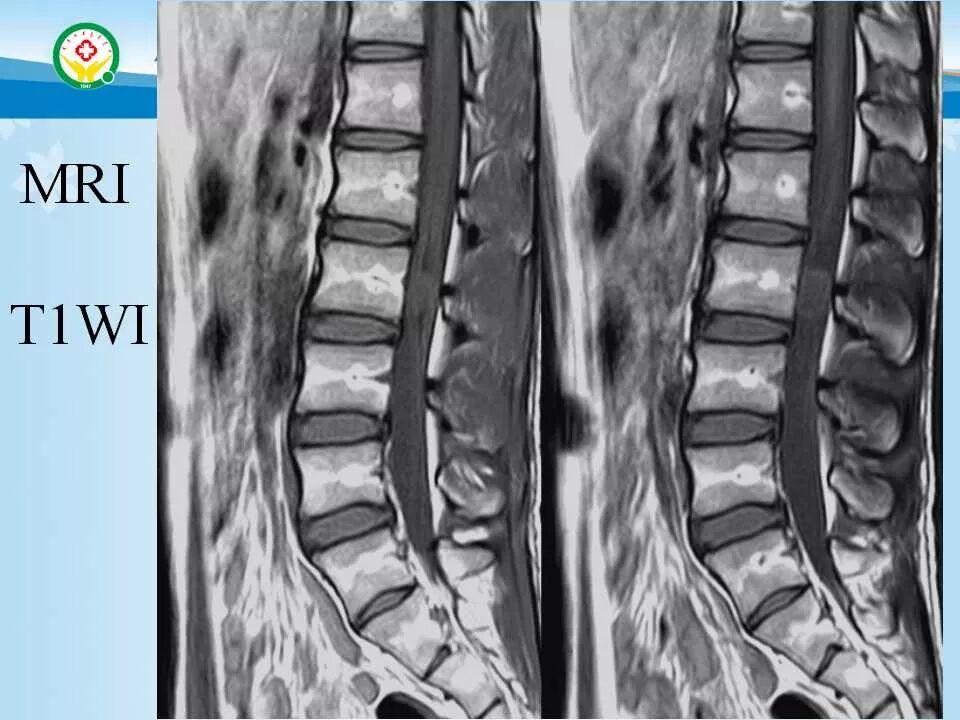

北方影像联盟 一周病例精选之“椎管占位”